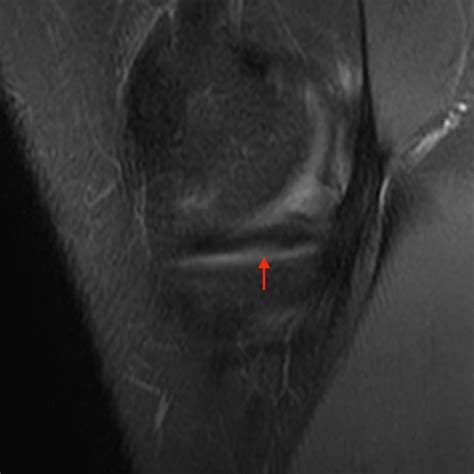

2. Imaging Tests: While X-rays are useful to rule out bone fractures, they cannot visualize the meniscus. An MRI (Magnetic Resonance Imaging) scan is the gold standard for diagnosing a bucket handle meniscus tear, as it provides detailed images of the soft tissue cartilage.